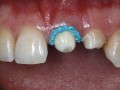

Zmodyfikowana technika ściany z tkanek miękkich (soft tissue…